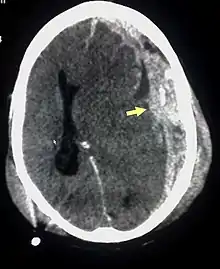

![]() Субдуральная гематома (обозначена стрелкой) со значительным смещением срединных структур. | |

При компьютерной томографии субдуральные гематомы имеют классическую серповидную форму, однако, могут выглядеть и линзовидно, особенно в начале кровотечения; это может вызвать затруднения в дифференциальной диагностике субдуральной и эпидуральной гематом. Более достоверным признаком субдуральной гематомы является её относительно большая распространённость по ходу полушария головного мозга с преодолением швов черепа, в отличие от эпидуральной гематомы. Субдуральная гематома также может выглядеть как «наслоение» повышенной плотности по ходу намёта мозжечка; такая гематома может быть хронической и стабильной, и косвенными минимальными признаками кровоизлияния могут служить сглаженность прилегающих борозд и медиальное смещение границы между серым и белым веществом.